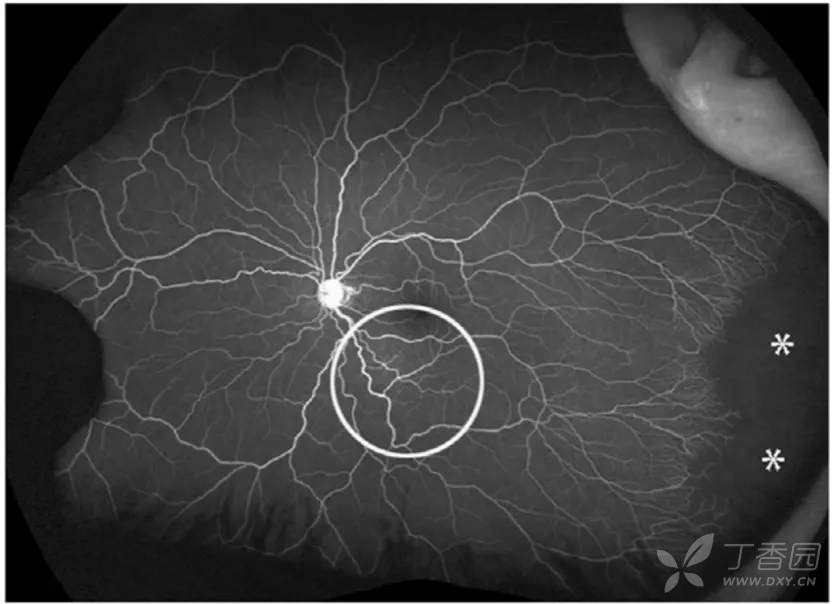

09、早产儿视网膜病变远期后遗症

图. 7岁患儿有自发消退ROP病史,超广角FA可见持续性视网膜无血管区(星号),颞下方异常的血管结构(圆圈)。

图. 7岁患儿有自发消退ROP病史,超广角FA可见颞下方不完全消退的3期病变处存在持续性视网膜无血管区和渗漏(星号)。